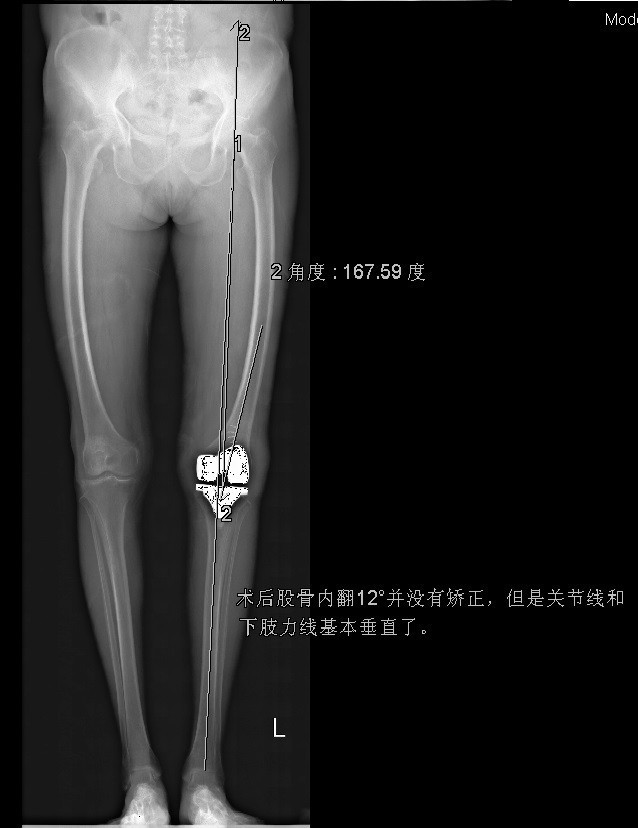

诊断:1、左膝骨关节炎伴屈曲畸形 2、左髌骨骨折骨愈合 治疗:积极行术前准备后于全麻下行左侧全膝关节置换术+软组织松解术,术后常规治疗。

患者术后功能良好,症状缓解,生活治疗提高 1、股骨外翻截骨如何在X线片上定角度?